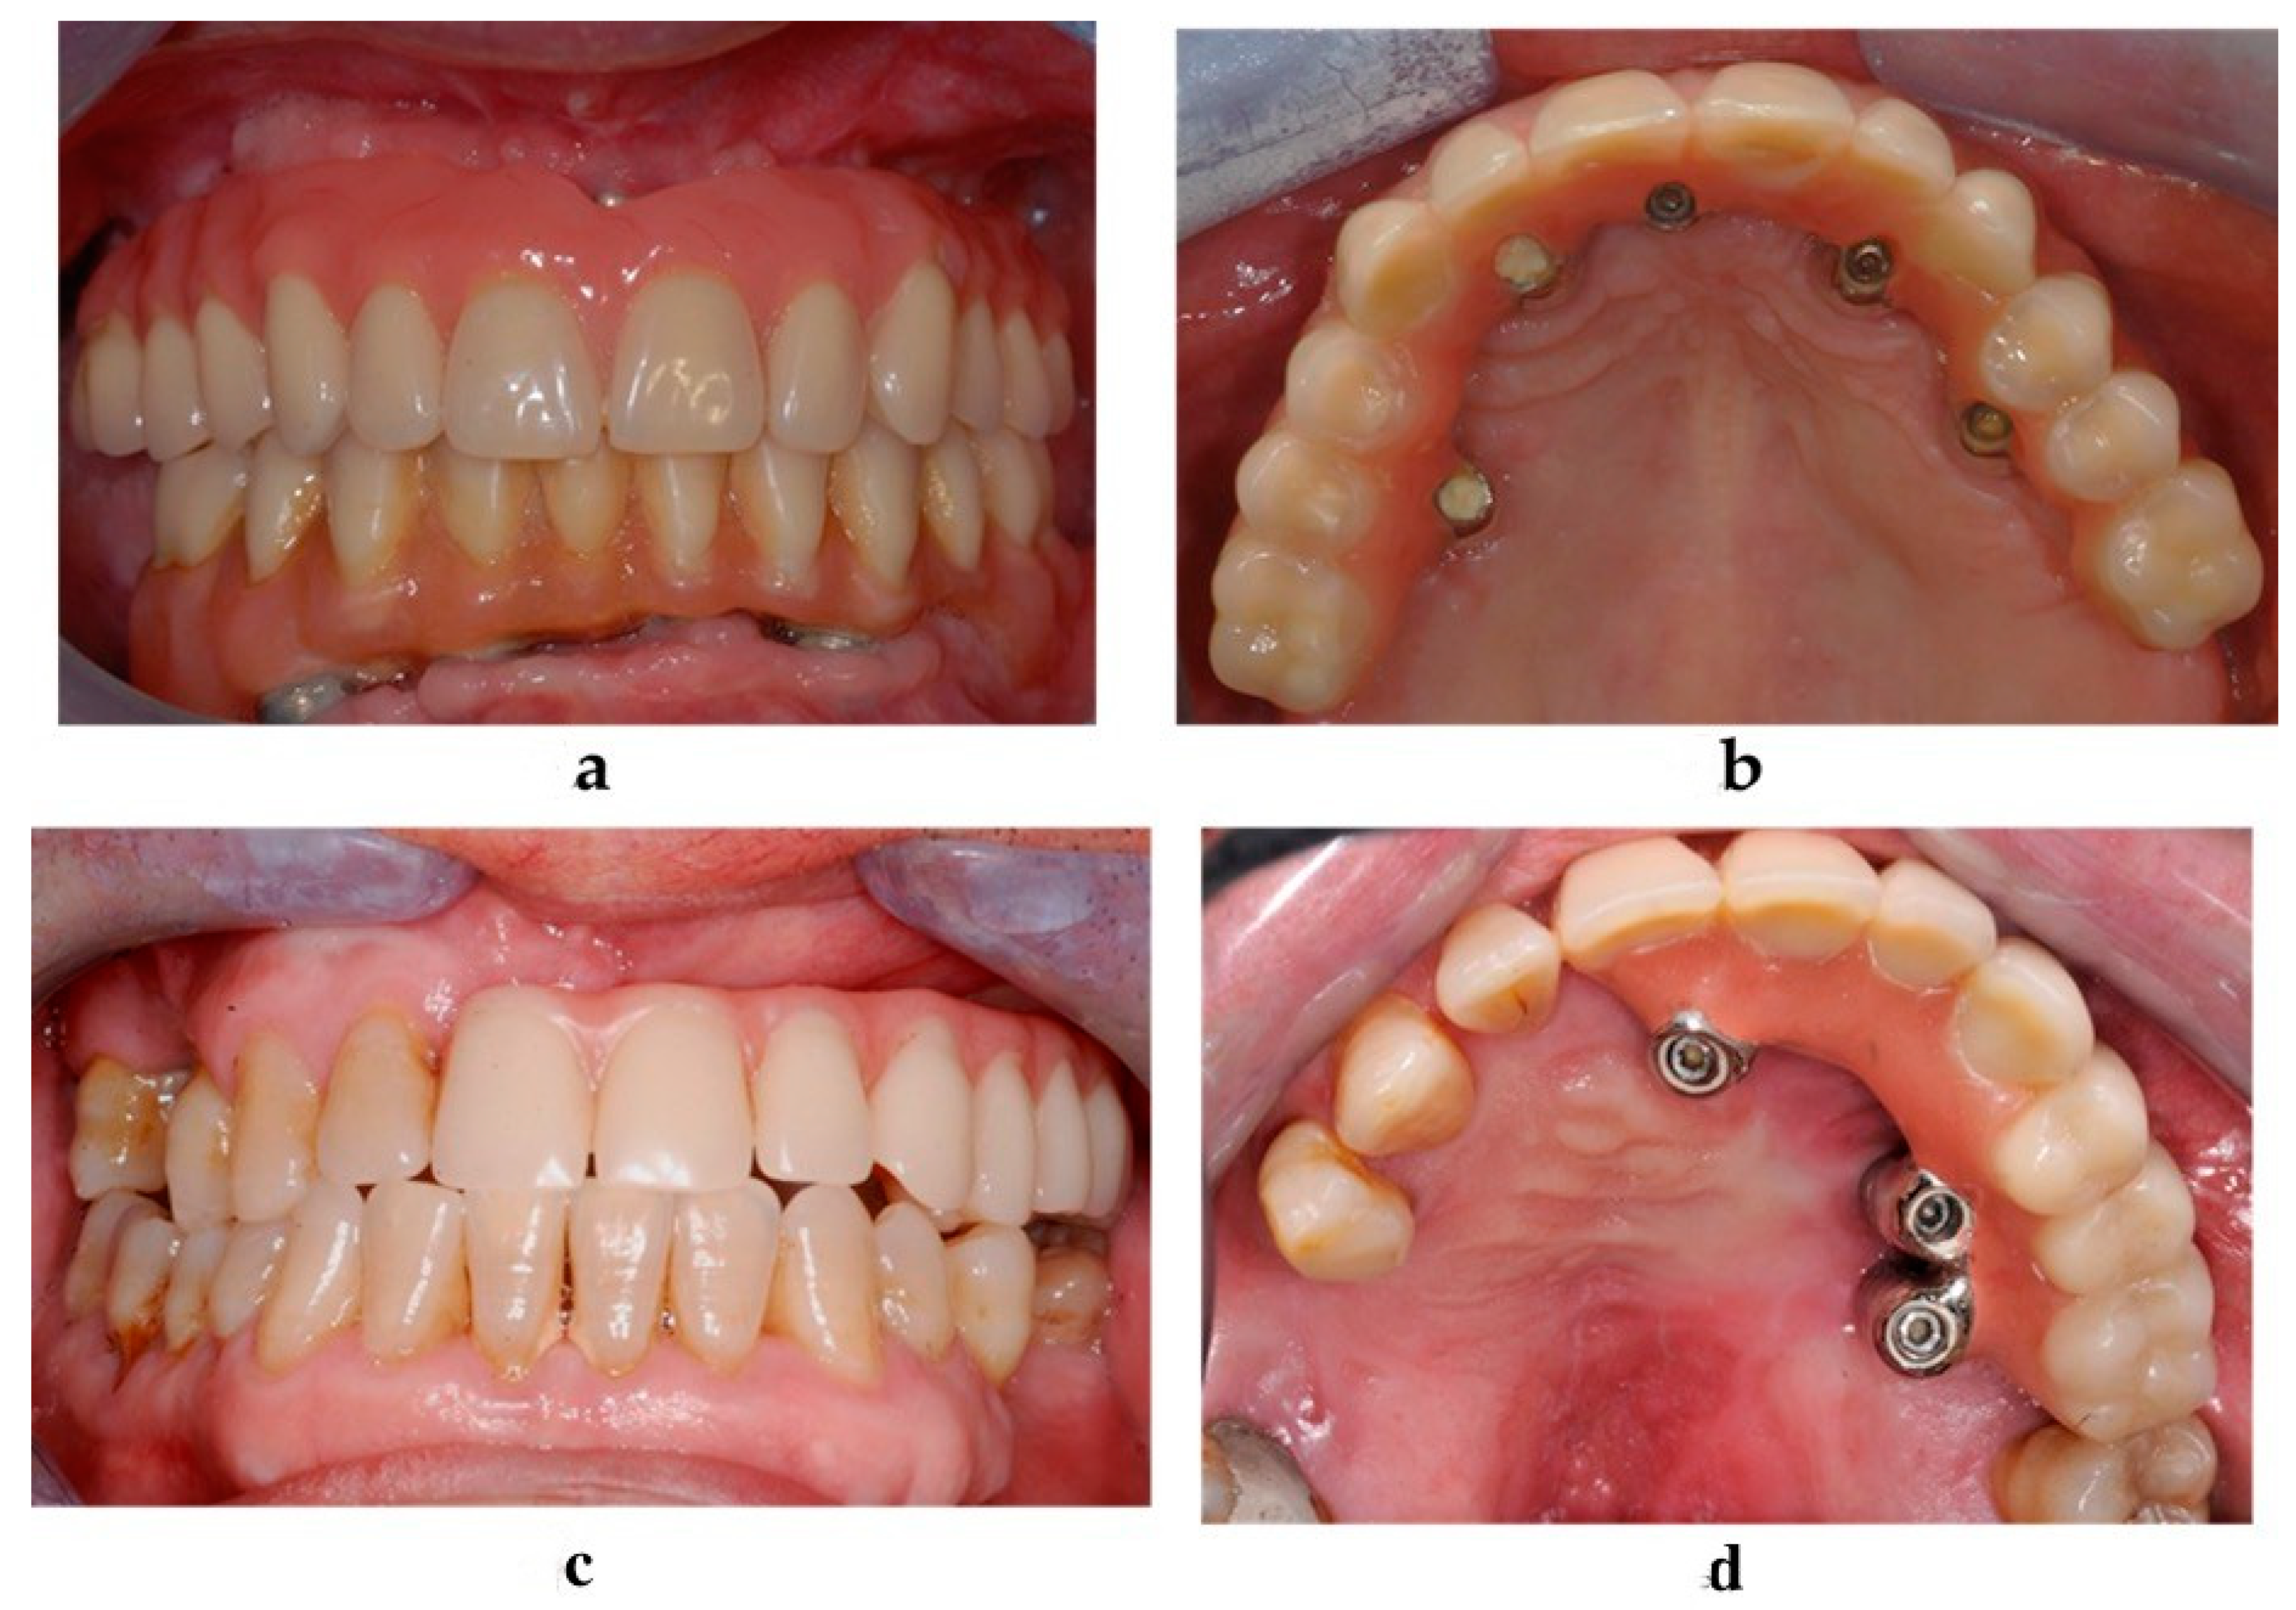

Figure 4. Clinical evaluation and soft tissue maintenance in the atrophic group (a,b) and in the oncologic group (c,d): frontal view (a), palatal view (b).

2.5. Clinical and Radiological Follow-Up

Clinical (Figure 4) and radiological follow-up visits were scheduled at 1, 6, 12, 18, 24, 36, 48, and 60 months after the implant placement.